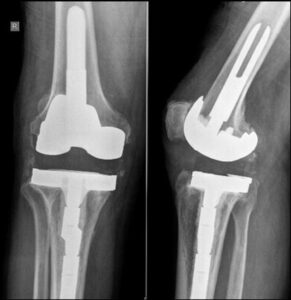

Infections related to joint replacements can either affect the surgical wound or develop deep within the area surrounding the artificial implants, which are made of metal and plastic. These infections can arise during the hospital stay or after the patient returns home, and in some cases, they may even occur years later.

However, joint replacements, which are made of metal and plastic, present a unique challenge for the immune system. Metal surfaces attract bacteria, and since these implants do not receive blood flow, the immune system has difficulty detecting and responding to bacterial presence around them. As a result, bacteria may colonize the metal implants, multiply, and lead to an infection in the joint.

Even with the use of antibiotics and preventive measures, patients with infected joint replacements often require surgical intervention to effectively treat the infection.